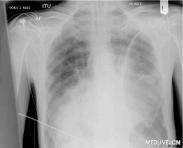

胸壁、肺、支氣管或食管上的創口呈單向活瓣,與胸膜腔相交通,吸氣時活瓣開放,空氣進入胸膜腔,呼氣時活瓣關閉,空氣不能從胸膜腔排出,因此隨著呼吸,傷側胸膜腔內壓力不斷增高,以致超過大氣壓,形成張力性氣胸,又稱壓力性氣胸或活瓣性氣胸。